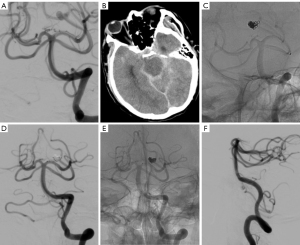

The procedure was successfully performed on all 49 patients, representing a 100% success rate. A total of 15 patients underwent stent-assisted embolization, totaling 17 stents. In one patient, two Neuroform Atlas stents were implanted simultaneously, and in another patient, one LVIS stent and one Enterprise stent were used. Among the stent-assisted embolization procedures, 13 used a single stent. Of these, 3 involved an Enterprise stent, 7 involved an LVIS stent, 1 involved a Neuroform Atlas stent, and 2 involved a Neuroform EZ stent. There were 34 patients who underwent simple coil embolization, accounting for 69.4% of all patients. The median number of coils used per aneurysm was 5.0 (IQR, 4.0–8.0). The median surgery time for all patients was 87.5 minutes (IQR, 63.8–106.3 minutes). A total of 4 patients (8.2%) underwent EVD. All patients received reconstructive endovascular treatment instead of parent artery sacrifice, and immediate postoperative angiography confirmed that all parent arteries were patent (Figure 2).